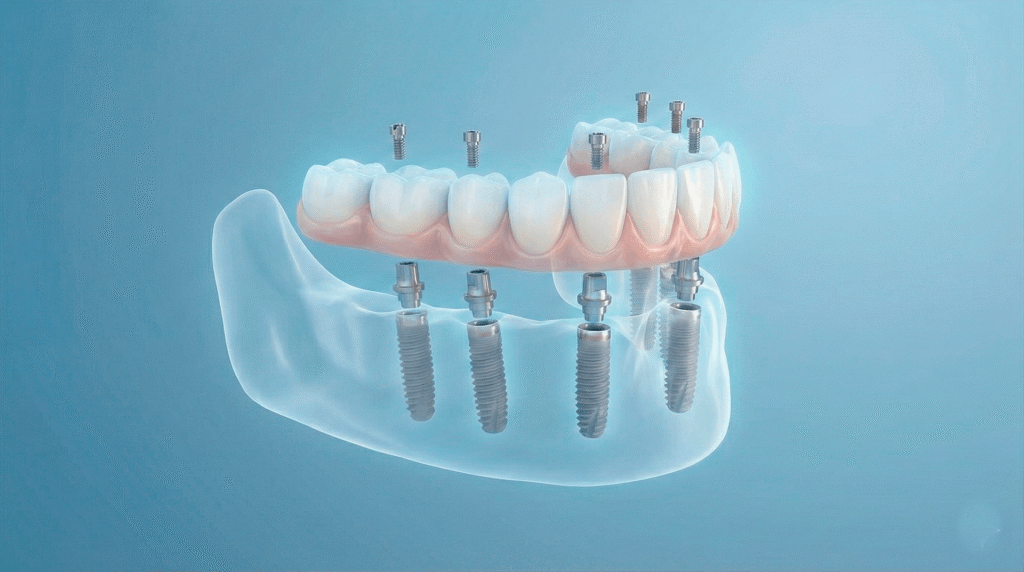

Metoda All-on-6 to zaawansowane rozwinięcie koncepcji pełnołukowej rekonstrukcji zgryzu. Polega ona na wprowadzeniu 6 implantów w żuchwę (dolny łuk) lub szczękę (górny łuk), co zapewnia jeszcze bardziej równomierne rozłożenie sił żucia i zwiększoną stabilność stałej pracy protetycznej.

Specyfikacja techniczna i biomechanika

W metodzie All-on-6 strategiczne rozmieszczenie sześciu punktów podparcia pozwala na uzyskanie optymalnej bazy dla mostu:

Rozkład sił

Zwiększona liczba wszczepów pozwala na lepszą dystrybucję obciążeń, co jest szczególnie istotne w przypadku szczęki (górnego łuku), gdzie gęstość kości jest naturalnie niższa niż w żuchwie.

Geometria wprowadzenia

Podobnie jak w systemie czteroimplantowym, część wszczepów może być wprowadzona pod kątem, aby optymalnie wykorzystać naturalne zasoby kostne pacjenta i uniknąć skomplikowanych zabiegów augmentacyjnych.